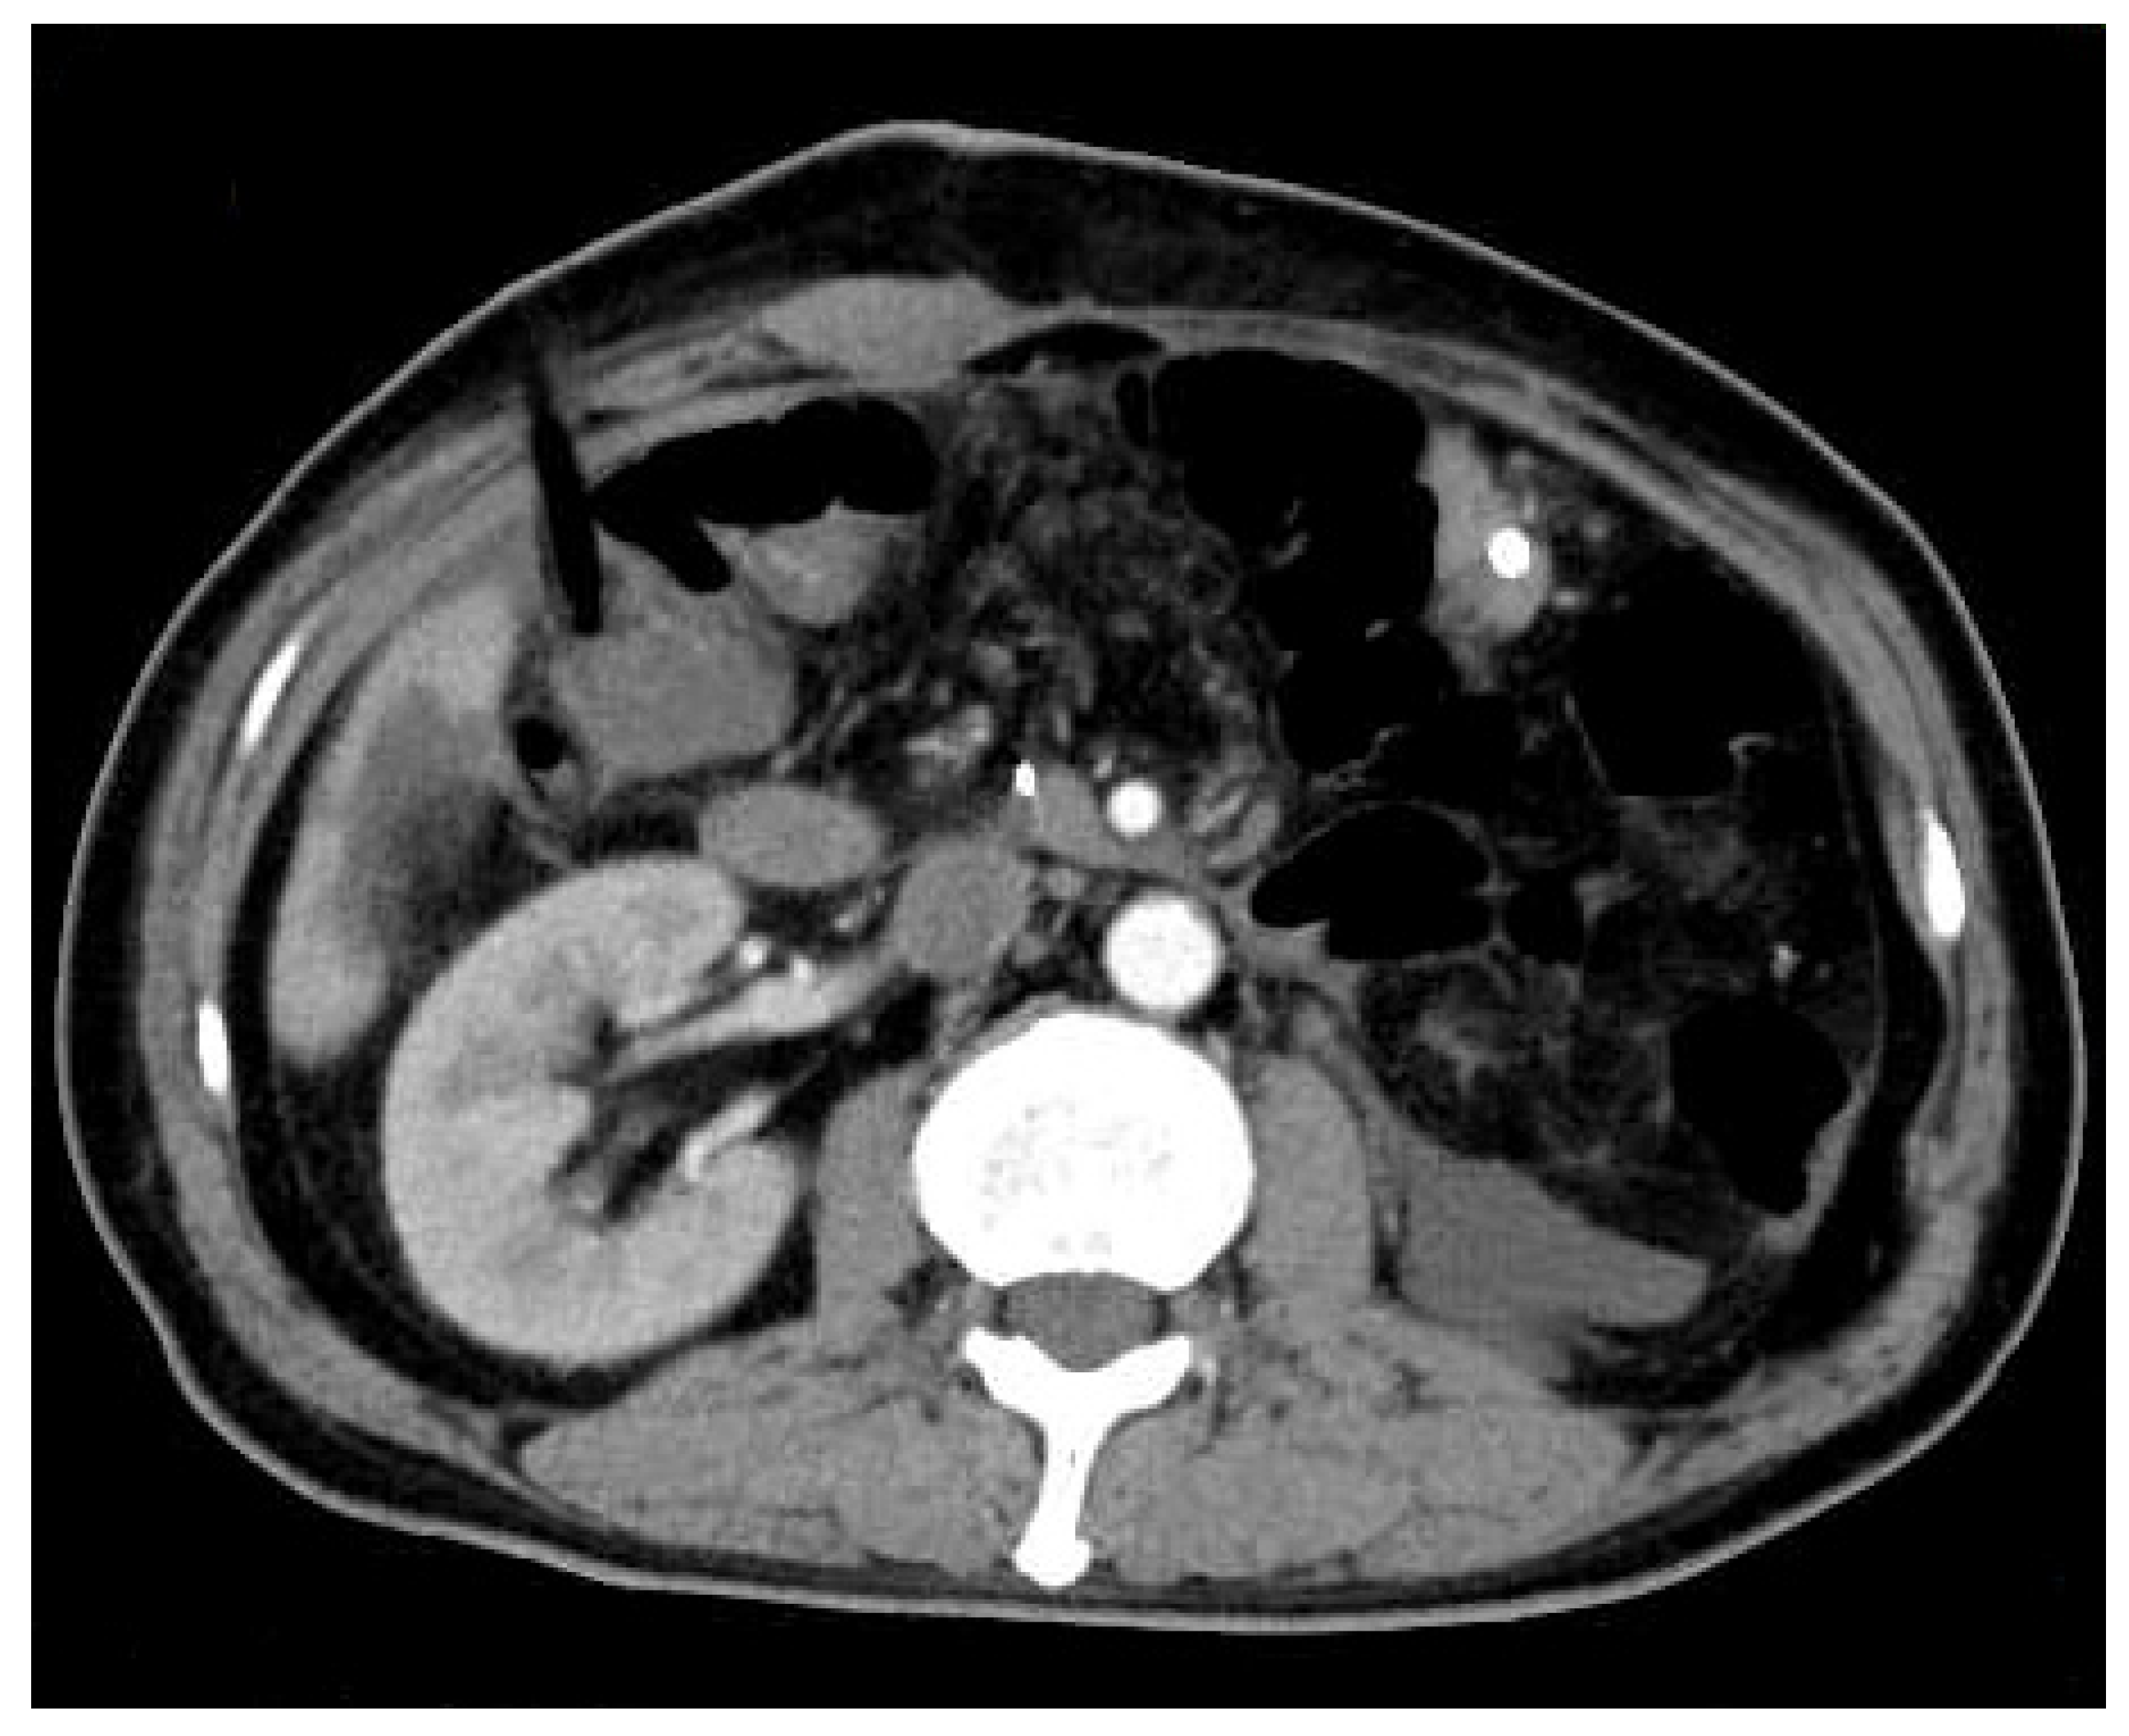

Abdominal enhanced computed tomography (CT) was rechecked on the fourth postoperative day. It showed no obvious effusion or residual lesion in the abdominal cavity.